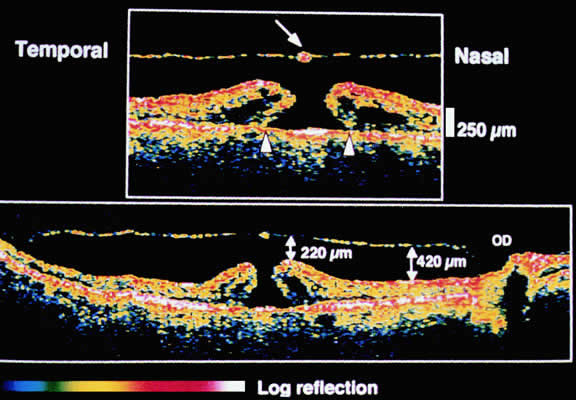

The mechanical relationship between the vitreous and the retina is mediated by the posterior vitreous cortex, which is also called the posterior hyaloid. The posterior vitreous cortex consists of relatively densely packed type II collagen fibrils arranged tangentially to the retina. The retinal basal lamina is the basement membrane of the Müller's cells that comprise the internal limiting membrane (ILM) of the retina.6,7 Ultrastructurally, the ILM consists of three layers.8 Adjacent to the end feet of the Müller's cells is the lamina rara interna. The lamina rara externa is contiguous with the vitreous cortex. In between these layers is the lamina densa. Collagen fibers of cortical vitreous are tangential to the lamina rara externa. The ILM is composed of primarily type IV collagen but also contains fibronectin, laminin, and type I collagen.9 The morphology of the ILM varies topographically in the retina. The ILM, and in particular the lamina densa, is thin in the retinal periphery and becomes increasingly thicker and irregular in the posterior retina.6,8

The ILM thickens from 50 nm at the vitreous base to 300 nm at the equator to 1900 nm posteriorly. In the foveal region the ILM thins to 10 to 20 nm.10

The nature of the adhesion between the vitreous cortex and the ILM is enigmatic. This adhesion is strongest at the optic nerve, the macula, the vitreous base, and retinal vessels. Foos6 demonstrated attachment plaques between Müller's cell cytoplasm and the ILM in the basal and equatorial retina (Fig. 2). Vitreous traction mediated by vitreous fibrils may contribute to these adhesions. These attachment plaques are not present posterior to the equator except where the ILM is thinned in the fovea. This anatomic variation in the fovea region may play a role in the pathogenesis of some of the vitreomacular disorders.

The ILM also thins over major blood vessels. Vitreous strands extend through pores in the ILM to surround the vessels11 and have been termed vitreoretinovascular bands.12 These bands may explain the strong adhesion between the vitreous and retinal vessels.